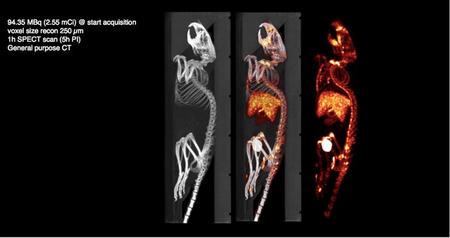

■SPECT装置およびX線CT装置で撮影した画像例(MOLECUBES社提供)

写真左から,X線CT画像,SPECT画像にX線CT画像を合わせた画像,SPECT画像